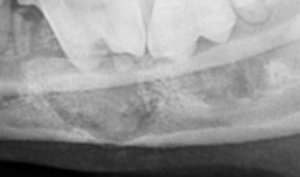

● 正常歯におけるレントゲンの撮影と読影法

ほぼ正常のデジタルレントゲン画像

( 無麻酔にて撮影 )

黄色のラインにて歯槽骨をトレースしております。このトレースラインにより、4番と5番の間は歯周病による50%歯槽骨の融解が認められることがわかります。その他の部位に関しましてはほぼ正常です。